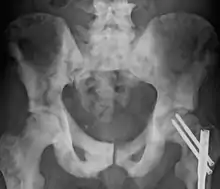

Sclerosis of the bones of the pelvis due to prostate cancer metastases

Osteosclerosis is a disorder that is characterized by abnormal hardening of bone and an elevation in bone density. It may predominantly affect the medullary portion and/or cortex of bone. Plain radiographs are a valuable tool for detecting and classifying osteosclerotic disorders.[1][2] It can manifest in localized or generalized osteosclerosis. Localized osteosclerosis can be caused by Legg–Calvé–Perthes disease, sickle-cell disease and osteoarthritis among others. Osteosclerosis can be classified in accordance with the causative factor into acquired and hereditary.[2][1]